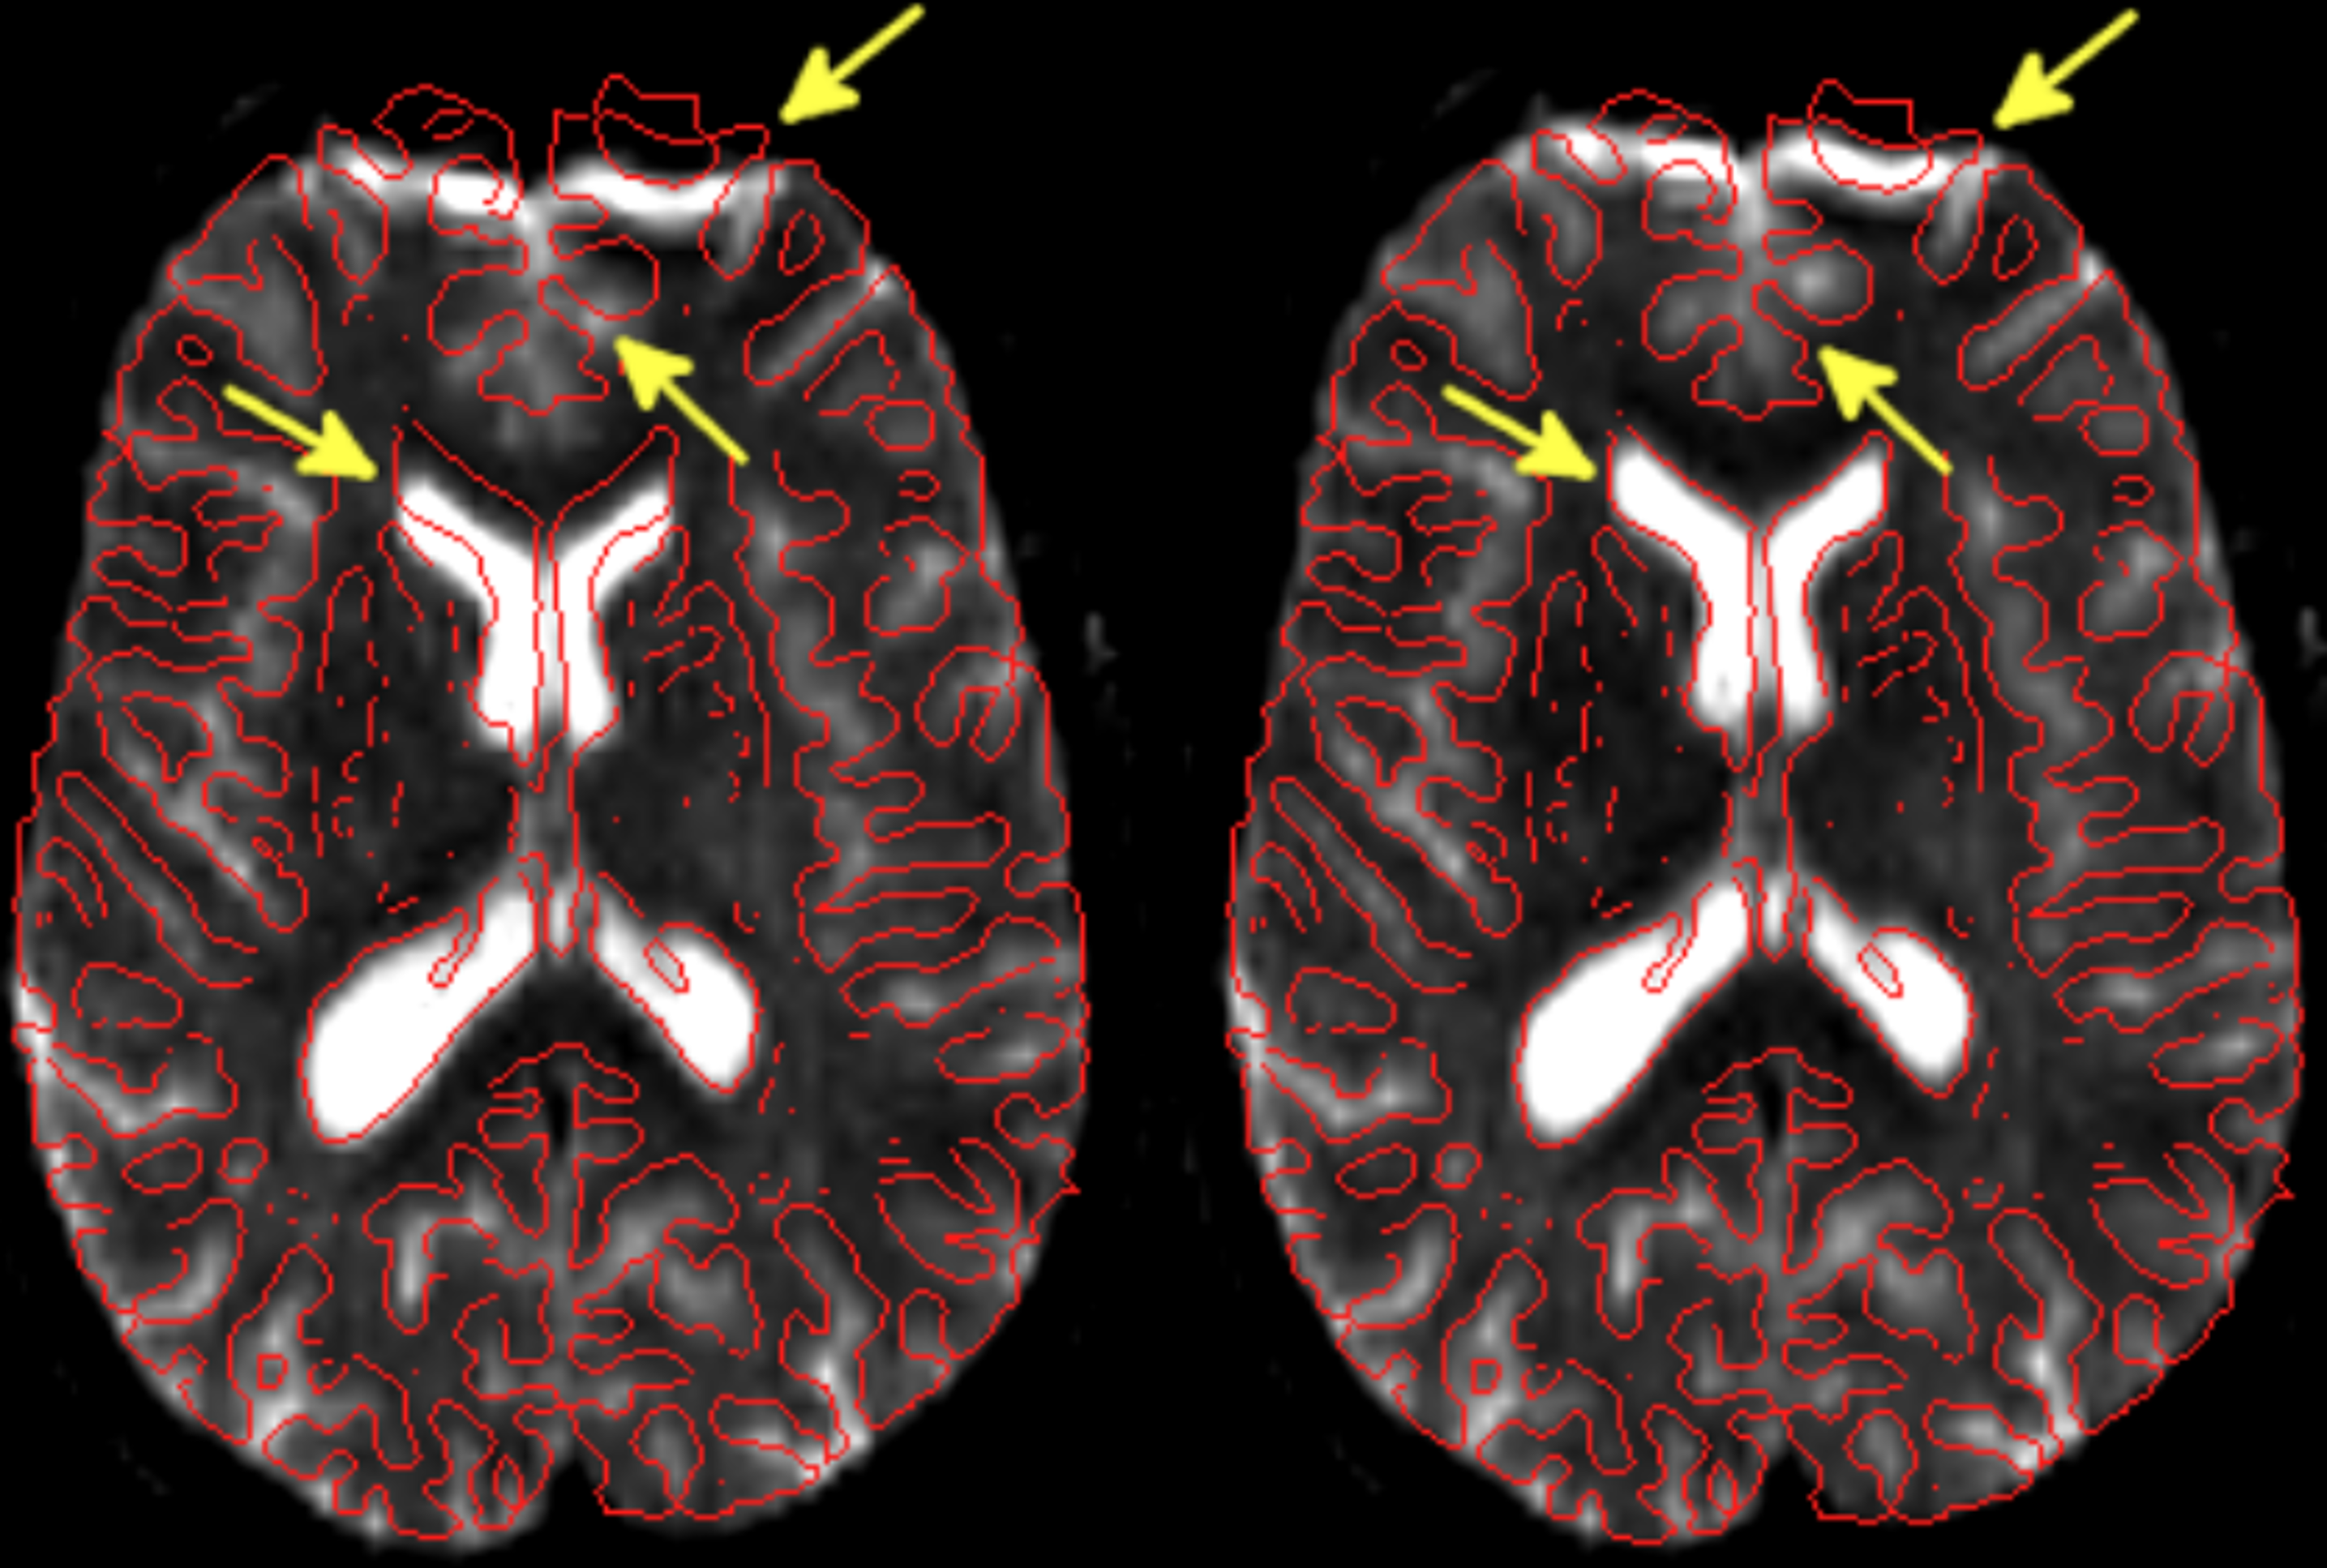

../_images/Phantom2D_data_spectroscopic_Im_3.png

Visualising Estimated Spectra for 2D Phantom Data